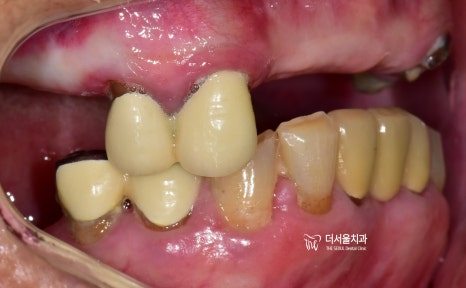

『임플란트 시술 결과』

남아있는 자연치아의 양 옆으로

나란히 1개씩 총 2개를 심어드렸습니다.

이후, 2개월뒤에 최종 보철까지

연결을 해드렸고

체크를 해둔 곳을 보면은, 한 쪽이

허공에 떠 있는 것을 보실 수 있죠?

바로 cantilever bridge 라는겁니다.